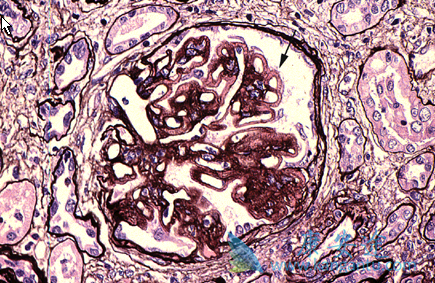

膜性肾病(MN)是成人肾病综合征的主要病因之一。随着近年来对原发性膜性肾病(PMN)的发病机制有了进一步了解,认为 PMN 是一种以产生针对足细胞上抗原的自身抗体为特点的一种自身免疫性疾病。利妥昔单抗(美罗华)是针对 B 淋巴细胞 CD20 的一种单克隆抗体,临床上多用于难治性肾病综合征的治疗。